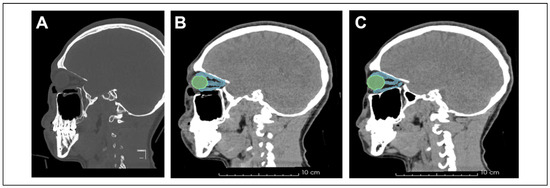

Intact Periorbita Can Prevent Post-Traumatic Enophthalmos Following a Large Orbital Blow-Out Fracture

Clinical Report